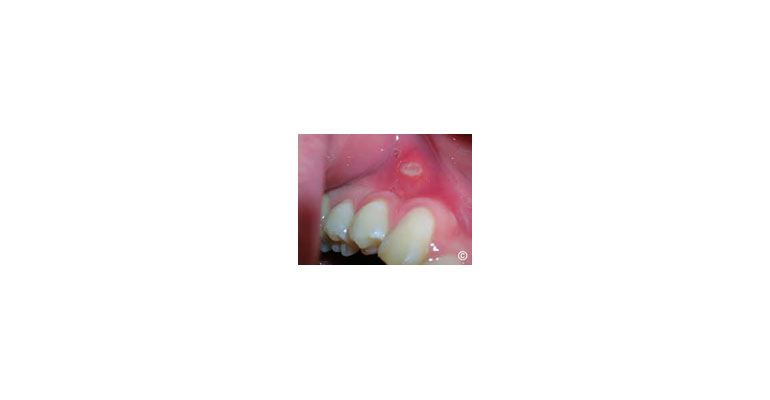

A case done by me to show it can be cured- earlier the better!

Canker Sores (Aphthous Ulcers):These are small, painful sores that typically appear on the inside of the lips, cheeks, or on the tongue. They are usually white or yellow with a red border and can be recurrent. The exact cause is not well understood but may be related to stress, dietary factors, or immune system issues.